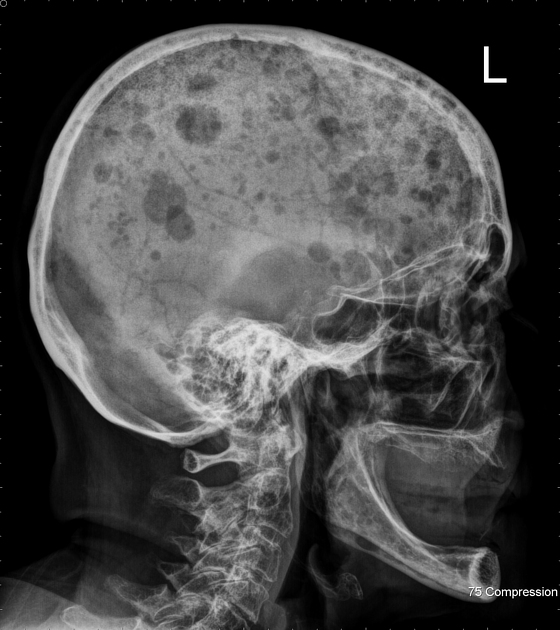

Diagnosis 진단

- Imaging: X-rays, MRI, and CT scans to detect bone lesions.

- 영상 검사: 뼈 병변을 감지하기 위한 X선, MRI 및 CT 스캔.